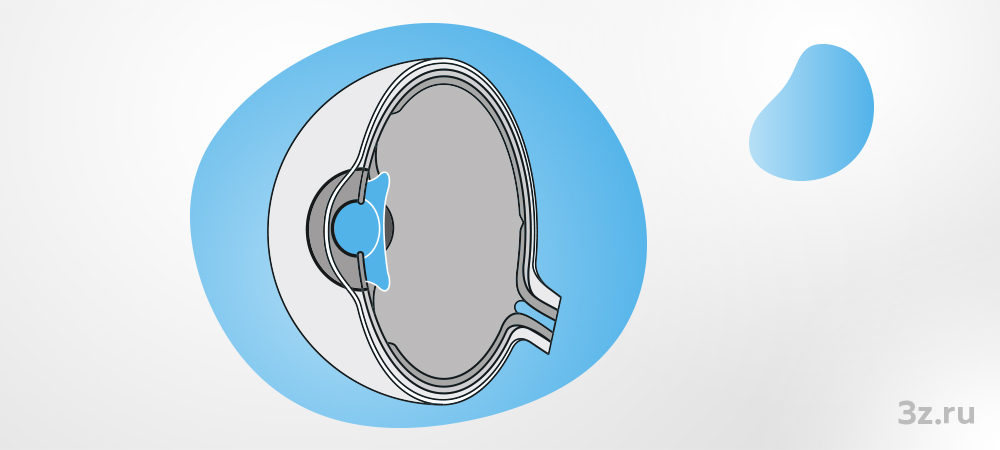

Памятка при имплантации ФИОЛ и пресбиФИОЛ

При коррекции зрения с помощью имплантации факичной интраокулярной линзы (ФИОЛ) или пресбиопической факичной интраокулярной линзы (пресбиФИОЛ) следует соблюдать все пред- и послеоперационные рекомендации.

- Подобрать совместно с офтальмохирургом факичную интраокулярную линзу (ФИОЛ) или пресбиопическую факичную интраокулярную линзу (пресбиФИОЛ).